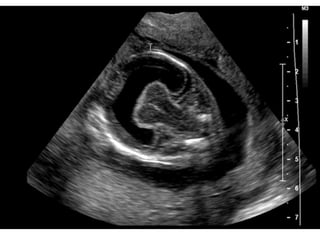

Edwards syndrome (Trisomy 18)

1st trimester

Increased nuchal translucency

2nd trimester

Multiple major anomalies

Single major anomaly + Trisomy 18 marker

Choroid plexus cyst + other anomalies

Early IUGR

IUGR

Cardiac defects

Muskuloskeletal findingd

-Clenched hands + overlapping index finger

Arthrogryposis

Rocker bottom foot

Clubfoot

Radial ray malformation

Cystic hygroma

Brain anomalies

Strawvberry shaped calvarium

Meningomyelocele

Facial anomalies

GI anomalies

SUA